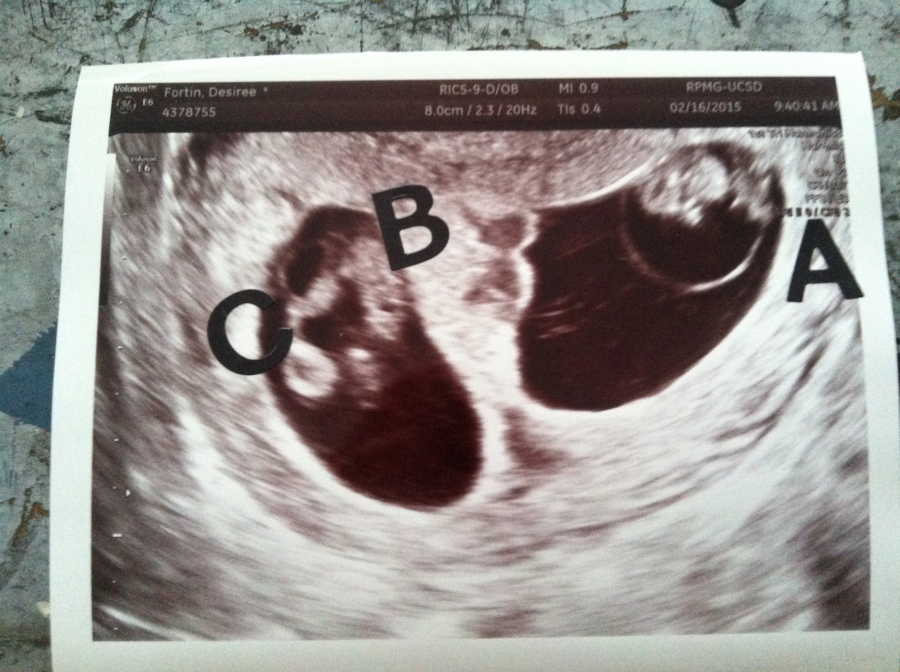

But the doctor didn’t stop; however, her expression grew serious as she moved the probe again. She could feel her chest tighten and Ryan’s hand trembling under hers. Another flicker appeared, and it was a third heartbeat. They were having Triplets. She stared at the screen as her mind struggled. It stumbled to make sense of it. One embryo split, creating identical twins, and the other was separate. Three babies. Her mouth went dry, and for a moment she couldn’t breathe. There was a rush of emotions: Excitement, fear, and disbelief all tangled together so tightly she wasn’t sure which feeling dominated.

The doctor spoke softly, explaining that transferring just one embryo was usually safest. The couple had hoped for twins. Triplets had never been part of their plan, but here they were, impossible and real at the same time. She closed her eyes for a second, trying to let it sink in, and then opened them again, looking at Ryan’s wide-eyed grin. Somehow, they were going to do this. Somehow, they were going to raise three children at once.